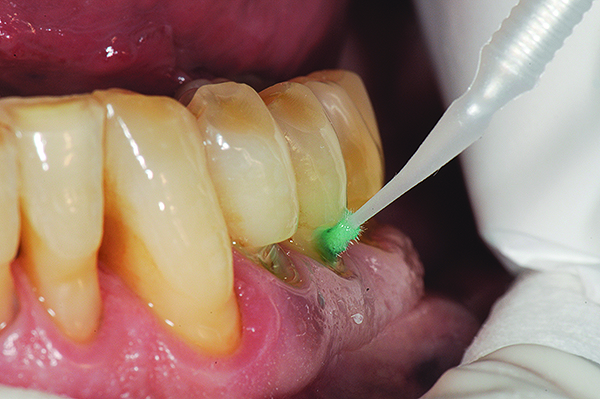

The case demonstrated in Figure 6 through Figure 11 shows the ease with which non-carious Class V lesions can be handled with bulk-filled GIC restorations. Several cervical lesions (abfractions) of significant depth in permanent posterior teeth showed signs of turning carious (Figure 6). The author elected to restore them with the EQUIA technique. For non-carious lesions it is only necessary to freshen the cavity surface and margins with a diamond or carbide bur and to remove any visibly damaged hard tissue. It is then most ideal to remove any smear layer by treating the cavities with a weak acidic solution such as 20% polyacrylic acid (Figure 7). It is important that the clinician not substitute this acidic solution with a conventional phosphoric acid solution or gel used for etching tooth structure prior to resin bonding, as using the conventional solution will remove important mineral content that the GIC requires to bond with chemically. Once the cavities were isolated, a high-viscosity auto-curing GIC was mixed and syringed into the cleaned cavities with a bulk-fill technique (Figure 8). A plastic instrument was then used to condense and shape the material to the cavity walls and margins. The GIC will set in approximately 2:30 seconds to a sufficient level where it is safe to begin adjusting and finishing with rotary instruments. After the restorations were finished, they were coated with a nanofilled, light-cured resin glaze (Figure 9 and Figure 10). The glaze protects the surface of the GIC while it sets completely and enhances the physical strength of the final restoration. The completed GIC restorations (Figure 11) showed excellent esthetics comparable to composite resin.

Fig 7. Cavities were cleaned with 20% polyacrylic acid solution.

Figure 7